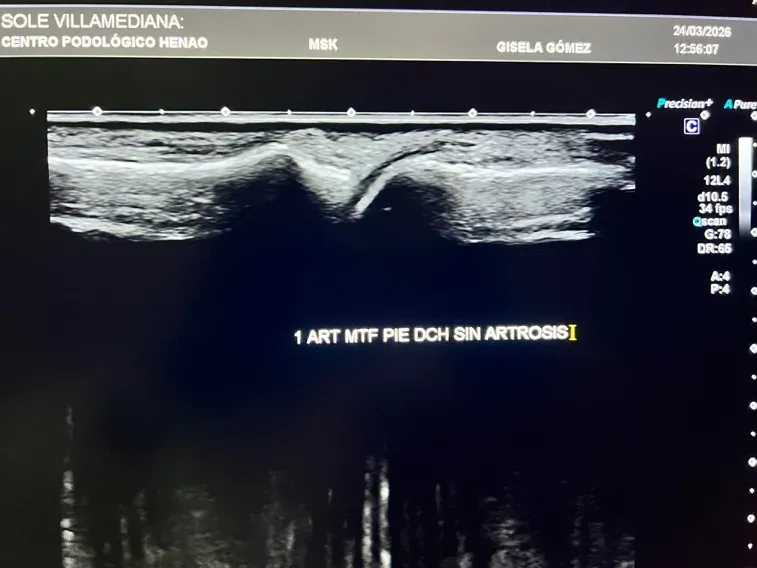

Lo que la ecografía sí detecta en fases tempranas

La ecografía musculoesquelética cambia por completo esta situación. Es una herramienta de diagnóstico por imagen que permite visualizar los tejidos blandos y las superficies articulares en tiempo real, sin radiación y con el paciente en la propia consulta.

En el contexto de la artrosis del pie, la ecografía detecta:

- Cambios en el cartílago articular: antes de que la radiografía muestre nada

- Irregularidades en la superficie articular: signos tempranos de desgaste

- Inflamación articular (sinovitis): presencia de líquido o engrosamiento de la membrana sinovial

- Derrame articular: acumulación de líquido dentro de la articulación

- Osteofitos en fases iniciales: formaciones óseas que aún no son visibles en radiografía

- Estado de los tejidos blandos periarticulares: cápsula, ligamentos, tendones adyacentes

Figura 2: Ecografía de una articulación del pie sin artrosis. Se aprecia un cartílago articular conservado, con superficie regular y sin signos de inflamación.